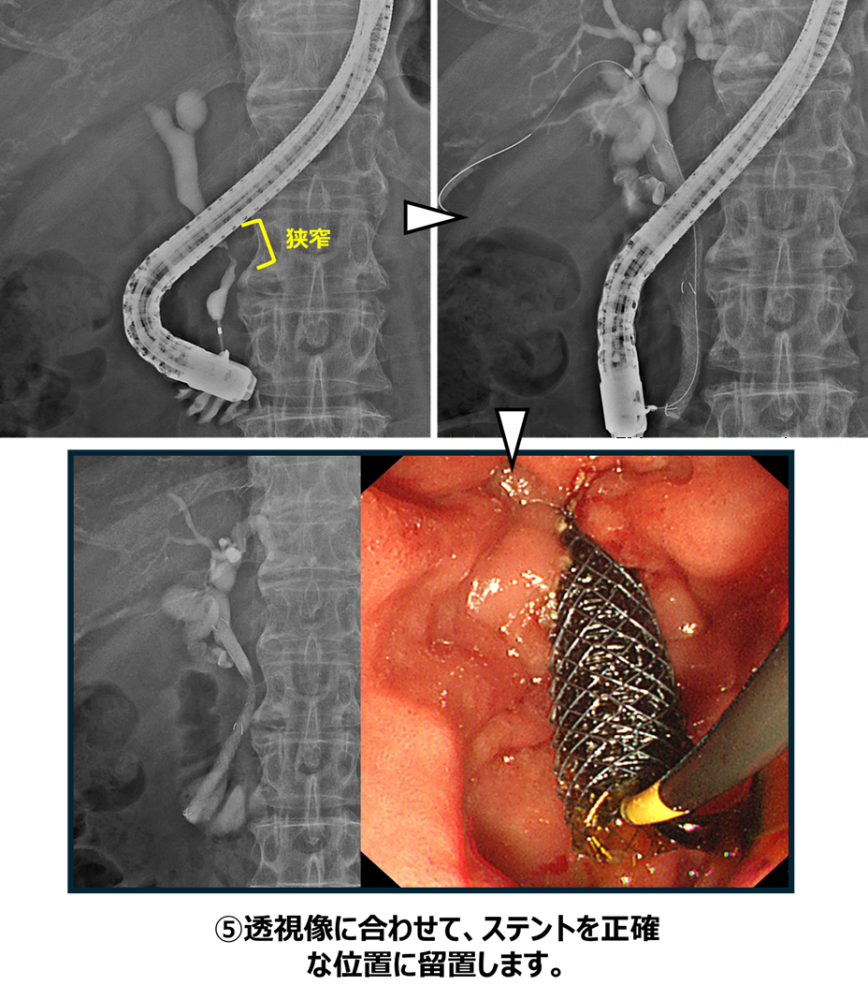

膵癌による胆道狭窄に対して胆道ドレナージを行った症例

膵癌に対して化学療法中でした。腫瘍によって、胆汁の流れ道である胆道が狭窄し、黄疸を発症し化学療法の中止を余儀なくされました。そのため、ERCPでの胆道ドレナージを行う方針としました。

まず内視鏡を十二指腸まで進め、胆管と膵管が合流する十二指腸乳頭(主乳頭)を確認します。専用のカテーテルを用いて胆管を選択し、ガイドワイヤーを胆管内へ挿入します。必要に応じて内視鏡的乳頭切開術を行い、胆管への処置を行いやすくします。これらの操作は透視装置(X線)で位置を確認しながら安全に進めます。

透視画像で胆道の狭窄を確認します。狭窄部は胆管の下流側にあり、この部位は遠位胆管と呼ばれます。この遠位胆管の狭窄部にステントを留置することで、胆汁の流れを改善します。本症例では金属ステントを1本留置し、胆汁の流れを確保しました。

本症例では高度の黄疸を認めていましたが、速やかに胆道ドレナージを行うことで黄疸は改善し、その後化学療法を再開することができました。